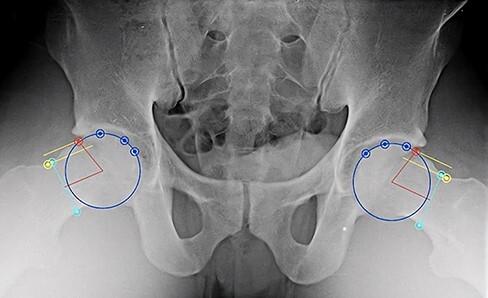

CAM-type femoroacetabular impingement continues to be an underrecognized cause of hip pain in elite athletes. Properties inherent to baseball such as throwing mechanics and hitting may enhance the risk of developing a cam deformity. Our goal is to gain an appreciation of the radiographic prevalence of cam deformities in elite baseball players. Prospective evaluation and radiographs of 80 elite baseball players were obtained during the 2016 preseason entrance examination. A sports medicine fellowship-trained orthopedic surgeon with experience treating hip disorders used standard radiographic measurements to assess for the radiographic presence of cam impingement. Radiographs with an alpha angle >55° on modified Dunn views were defined as cam positive. Of the 122 elite baseball players included in our analysis, 80 completed radiographic evaluation. Only 7.3% (9/122) of players reported hip pain and 1.6% (4/244) had a positive anterior impingement test. The prevalence of cam deformities in right and left hips were 54/80 (67.5%) and 40/80 (50.0%), respectively. The mean alpha angle for cam-positive right and left hips were 64.7 ± 6.9° and 64.9 ± 5.8°, respectively. Outfielders had the highest risk of right-sided cam morphology (Relative Risk (RR) = 1.6). Right hip cam deformities were significantly higher in right-handed pitchers compared with left-handed pitchers ( = 0.02); however, there was no significant difference in left hip cam deformities between left- and right-handed pitchers ( = 0.307). Our data suggest that elite baseball players have a significantly higher prevalence of radiographic cam impingement than the general population.

凸轮型股骨髋臼撞击症仍是精英运动员髋部疼痛的一个未被充分认识的原因。棒球运动固有的特性,如投球动作和击球,可能会增加发生凸轮畸形的风险。我们的目标是了解精英棒球运动员中凸轮畸形的影像学患病率。在2016年季前入学考试期间,对80名精英棒球运动员进行了前瞻性评估并拍摄了X光片。一位接受过运动医学专科培训且有髋部疾病治疗经验的骨科医生使用标准影像学测量方法来评估凸轮撞击症的影像学表现。改良邓恩视图上α角>55°的X光片被定义为凸轮阳性。在我们分析的122名精英棒球运动员中,80人完成了影像学评估。只有7.3%(9/122)的运动员报告有髋部疼痛,1.6%(4/244)的运动员前撞击试验呈阳性。右髋和左髋凸轮畸形的患病率分别为54/80(67.5%)和40/80(50.0%)。凸轮阳性的右髋和左髋的平均α角分别为64.7±6.9°和64.9±5.8°。外场手右侧凸轮形态的风险最高(相对风险(RR)=1.6)。与左撇子投手相比,右撇子投手的右髋凸轮畸形明显更高(P=0.02);然而,左撇子和右撇子投手的左髋凸轮畸形没有显著差异(P=0.307)。我们的数据表明,精英棒球运动员影像学凸轮撞击症的患病率明显高于普通人群。